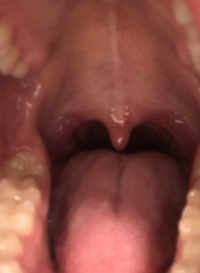

閲覧注意 この喉ちんこは正常でしょうか 最近声が詰まる 喋るとガラガラ声にな Yahoo 知恵袋